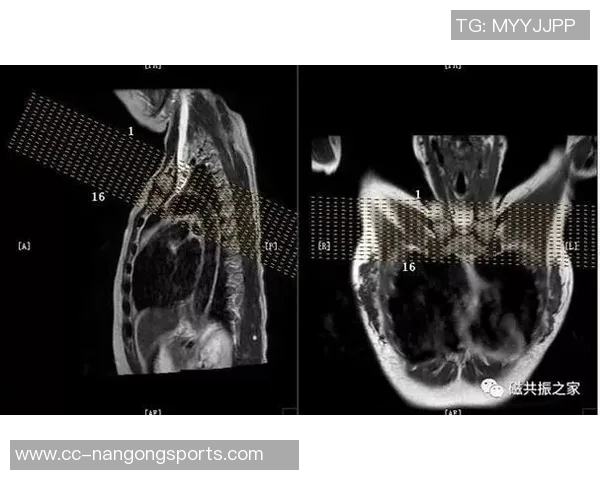

MRI(磁共振成像)是一种无创性的高分辨率影像学技术,可以清楚地显示软组织结构,因此对于评估肌肉、韧带和其他组织的损伤尤为重要。这也是为什么医生会选择第二次检查,以确保全面了解约维奇的实际情况。

幸运的是,通过X光结果显示并未发现明显异常,这意味着目前没有骨折或严重损害的迹象。然而,这并不代表他完全没有危险,因为软组织损伤如韧带扭伤等问题仍然需要进一步确认。因此,医生建议进行MRI检查以获得更详细的信息。